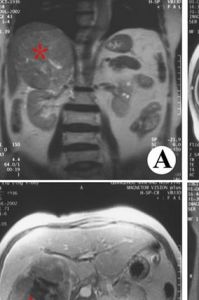

隨著B超、CT的廣泛套用,腎上腺皮質癌檢出率有增高趨勢,二者對診斷腎上腺皮質癌具有非常重要的價值。腎上腺皮質癌的CT主要表現為一般瘤體較大,直徑可達7~20cm,多數有包膜,呈分葉狀,瘤內可有廣泛出血、壞死和鈣化,表現為多種不同密度的混合性腫塊。又因為腫瘤較大,常對周圍組織和器官造成擠壓推移現象。若同時看到腹膜後的淋巴結腫大,或在肝、腎內出現轉移灶,對判斷腫瘤的良、惡性更有意義。

無功能性腎上腺皮質癌臨床表現隱匿,缺乏特徵性,患者多以腰痛、腹痛就診,早期診斷困難,腫瘤多為行B超、CT檢查時偶然發現。目前B超和CT為腫瘤早期定位診斷的主要手段,對臨床分期、手術難易程度、預後判斷有重要意義,但對確定腫瘤性質仍有一定困難。一般來說,腫瘤越大惡性變的可能性越大。在臨床上,對於偶發性腫瘤,如直徑大於3.5cm,均應手術處理。對於腫瘤直徑小於3.5cm,如果腫瘤外形光滑,邊緣清晰,呈圓形或卵圓形低密度影,與鄰近組織界限清楚,表現為良性生物學行為,可行B超、CT隨診,暫不行手術治療[6,7]。B超作為一項簡便的影像學檢查方法,可作為健康人查體的首選項目。一旦發現腹膜後腫物,再結合CT等檢查方法,可達早期治療的目的。本組1例女性患者於查體行B超檢查時偶然發現右腎上腺腫物,行手術切除,報告為腎上腺皮質癌,現術後1年無復發。